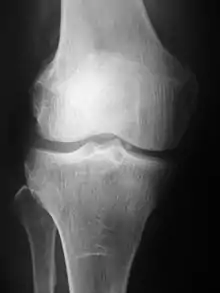

Radiographs (originally called roentgenographs, named after the discoverer of X-rays, Wilhelm Conrad Röntgen) are produced by transmitting X-rays through a patient. The X-rays are projected through the body onto a detector; an image is formed based on which rays pass through (and are detected) versus those that are absorbed or scattered in the patient (and thus are not detected). Röntgen discovered X-rays on November 8, 1895, and received the first Nobel Prize in Physics for his discovery in 1901.

Plain radiography was the only imaging modality available during the first 50 years of radiology. Due to its availability, speed, and lower costs compared to other modalities, radiography is often the first-line test of choice in radiologic diagnosis. Also despite the large amount of data in CT scans, MR scans and other digital-based imaging, there are many disease entities in which the classic diagnosis is obtained by plain radiographs. Examples include various types of arthritis and pneumonia, bone tumors (especially benign bone tumors), fractures, congenital skeletal anomalies, and certain kidney stones.